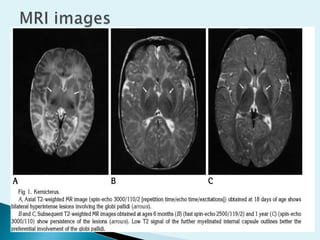

Axial (A) and coronal

(B) T1-weighted

and axial FLAIR (C)

images at the

level of the basal

ganglia show

symmetric,

hyperintense globus

pallidusinvolvement.

This is not apparent

onthe axial T2-

weighted (D) image.

(From Coskun A, et

al: Hyperintense

globus pallidus on

T1-weighted MR

imaging in acute

kernicterus:

. Axial (A) andcoronal (B) T1-weighted and axial FLAIR (C) images at the level of the basal ganglia show symmetric, hyperintense globus pallidusinvolvement. This is not apparent onthe axial T2- weighted (D) image. (From Coskun A, et al: Hyperintense globus pallidus on T1-weighted MR imaging in acute kernicterus: